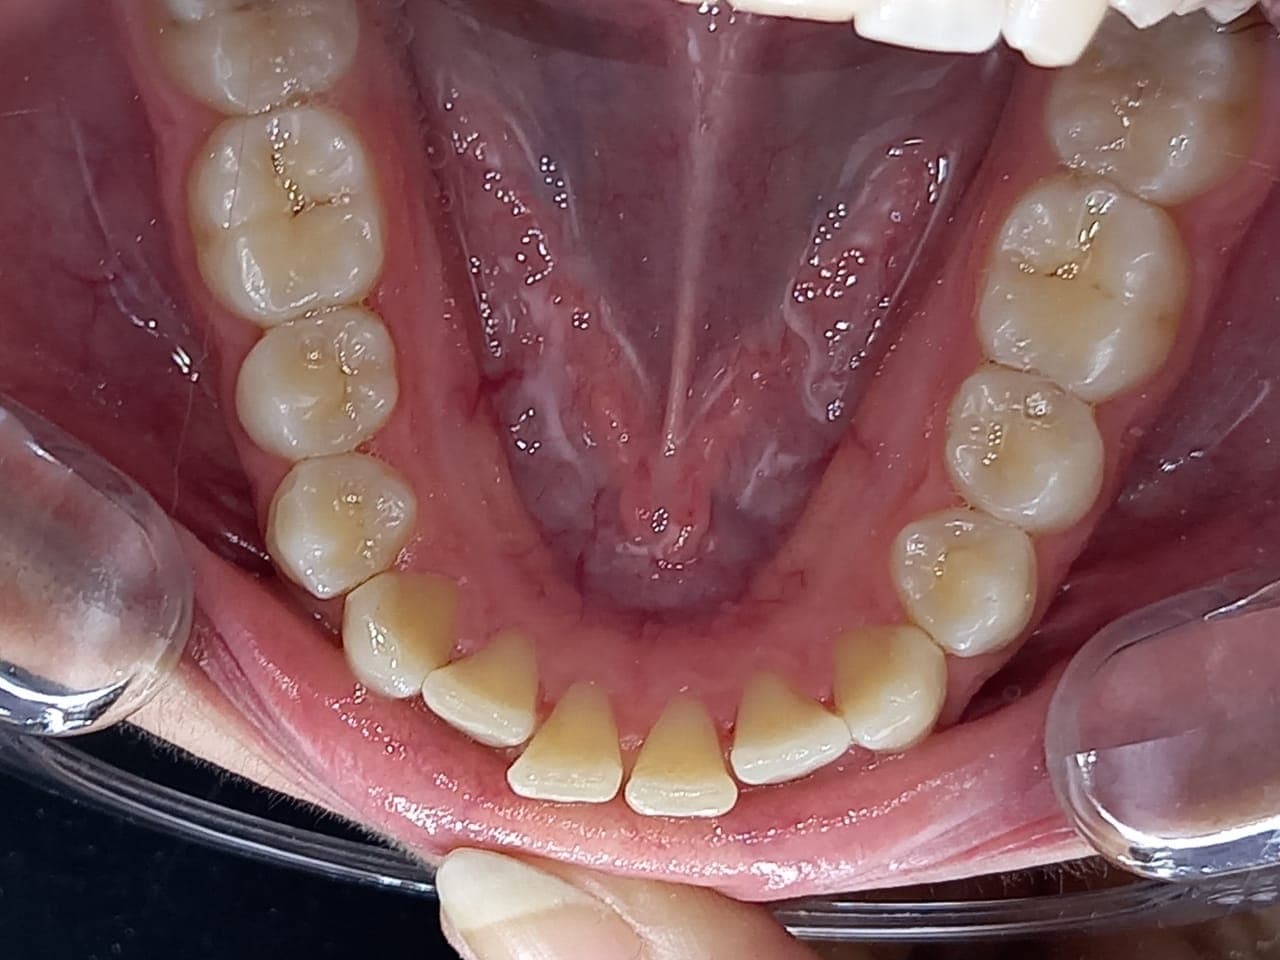

Middle of treatment

Crowding reduces as aligners create space between teeth through controlled movement. The arch expands, and tooth rotations become more visible.

End of treatment

Teeth reach full alignment. Spaces close, crowding resolves, and the arch appears symmetrical and balanced, consistent with the treatment plan.